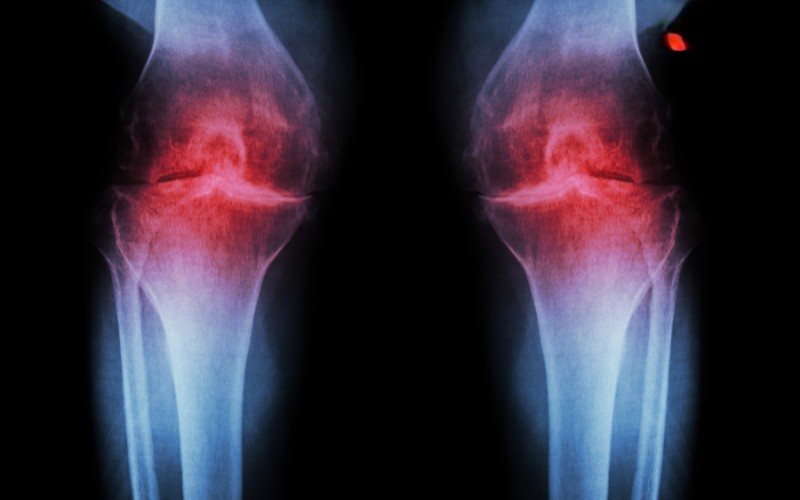

dự đoán hình ảnh

Các phương pháp dự đoán hình ảnh giúp đánh giá cấu trúc gối đầu, xác định mức độ dịch chuyển và tổn thương kèm theo.